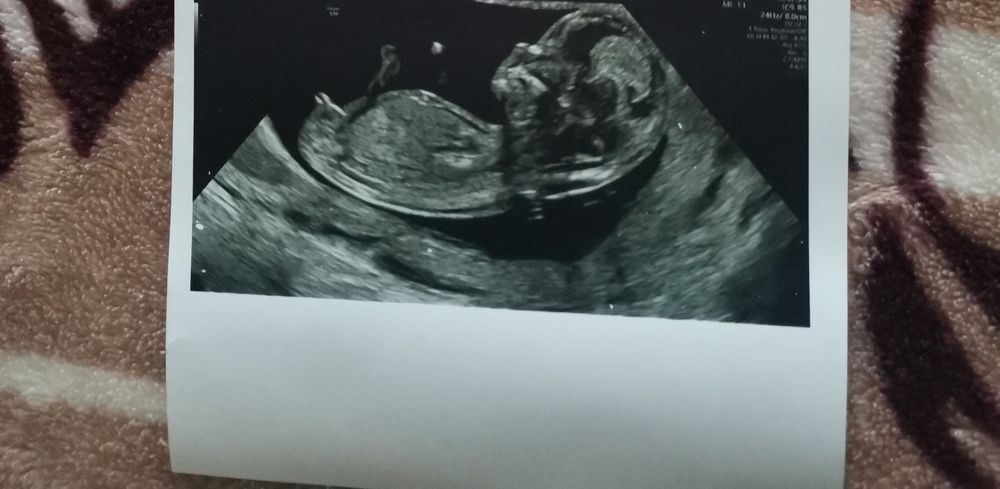

жду мальчика, 16 неделя Москва

Половой бугорок в 12 недель

Это девочка, у мальчиков выше градус, а тут прям параллельно позвоночнику. Прям так чётко еще видно. Вот по смотрите даже сами Изображение

Больше к девочке наклон)

Елена, а врачу показала фото сказал 70%мальчик

Многие говорят, что до 16 недель не информативно. Лучше кровь